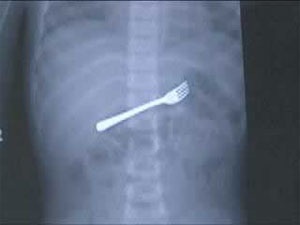

Dĩa ăn.